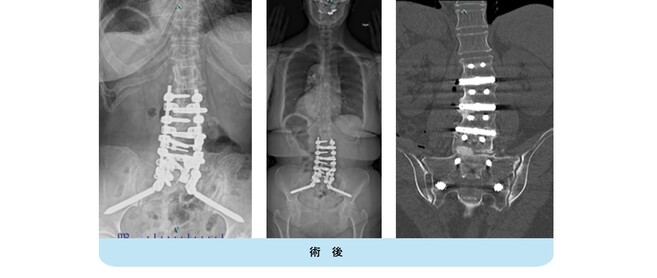

変性側弯症の患者さんで、難治性の腰痛と夜間も続く坐骨神経痛のために日常生活が困難でした。下位腰仙椎の多椎間で変性、側弯変形を認めます。

腰仙椎前方後方同時固定術による側弯変形の矯正、神経の除圧を行いました。悩んでいた腰痛がなくなり、坐骨神経痛が無くなったため夜間も穏やかに眠れるようになりました。